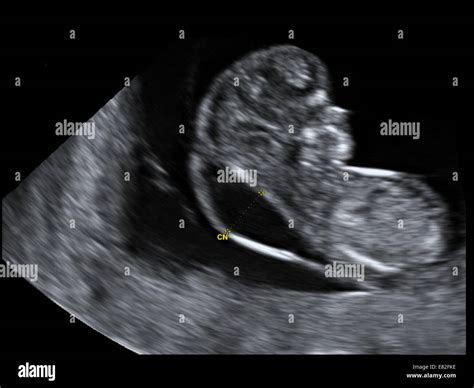

The Nuchal Screening Ultrasound, frequently referred to as the Nuchal Translucency (NT) scan, is a non-invasive diagnostic procedure performed between 11 and 14 weeks of pregnancy. During this examination, a sonographer uses ultrasound technology to measure the clear space in the tissue at the back of the baby’s neck. This area, known as the nuchal translucency, contains a small amount of fluid. While all fetuses have some fluid in this region, a measurement that is larger than average can be an indicator of an increased risk for chromosomal conditions, such as Down syndrome (trisomy 21), Edwards syndrome (trisomy 18), or Patau syndrome (trisomy 13), as well as certain structural heart defects.

• Crown-Rump Length (CRL): To accurately determine the gestational age of the fetus.

• Nuchal Translucency Thickness: The core focus of the screening.

• Fetal Anatomy: A preliminary look at the baby's development, including the skull, spine, heart, and limbs.

• Presence of Nasal Bone: Research shows that the absence of a visible nasal bone in the first trimester is sometimes associated with a higher risk of chromosomal abnormalities.